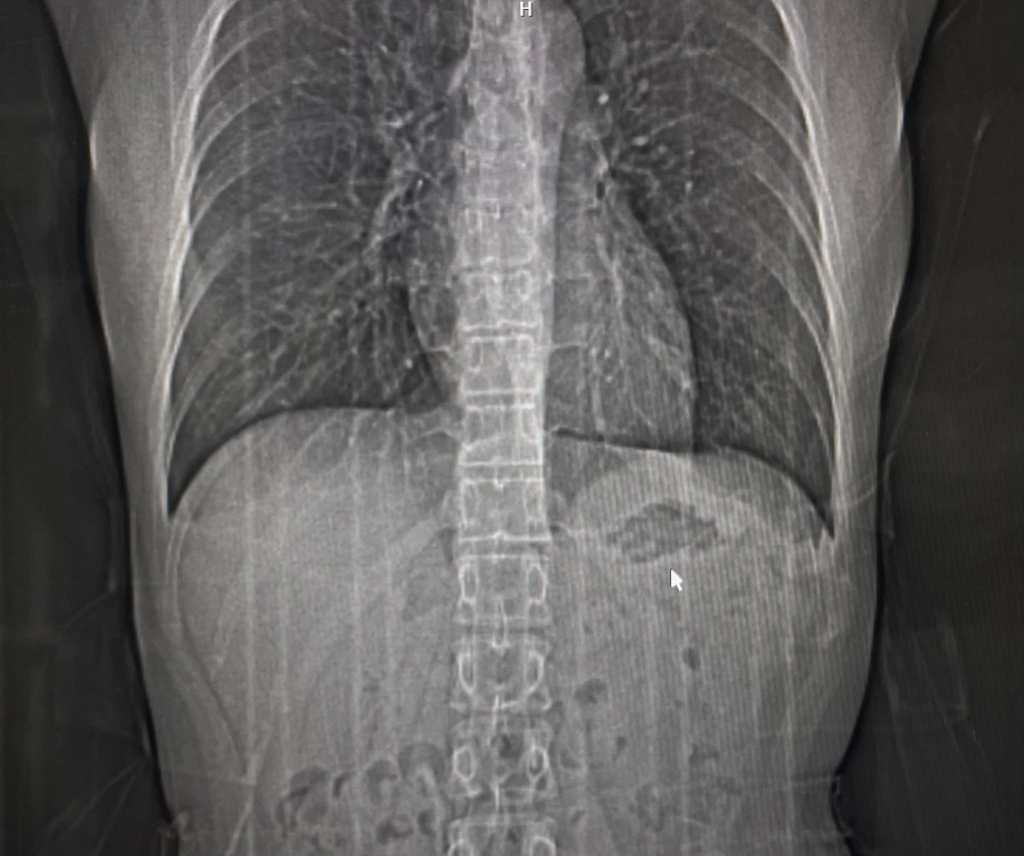

왼쪽 갈비뼈에 혹같은 게 만져져서

건강검진때 폐CT를 찍었는데요.

마우스가 가리키고 있는 게 무엇인지 궁금합니다.

저 마우스가 있는 쪽이 왼쪽도 맞는거죠???

안녕하세요. 채홍석 의사입니다. 좌상복부에 보이는 어두운 음영 말씀이죠?

저건 위 (stomach) 내부에 있는 공기(gas) 입니다.

정확한 상태에 대한 진단은 알 수 없으나 해당 부위는 복부의 위가 위치한 부위로, 위에 가스가 차 있을 때 나타날 수 있는 소견입니다. 방향은 질문자님께서 말씀하신대로 왼쪽이 맞습니다. 다만 정확한 판독은 영상의학과에서 받아보시는 것이 좋을 것으로 사료됩니다.

네 왼쪽이 맞고 위장의 가스가 보이는 음영입니다.